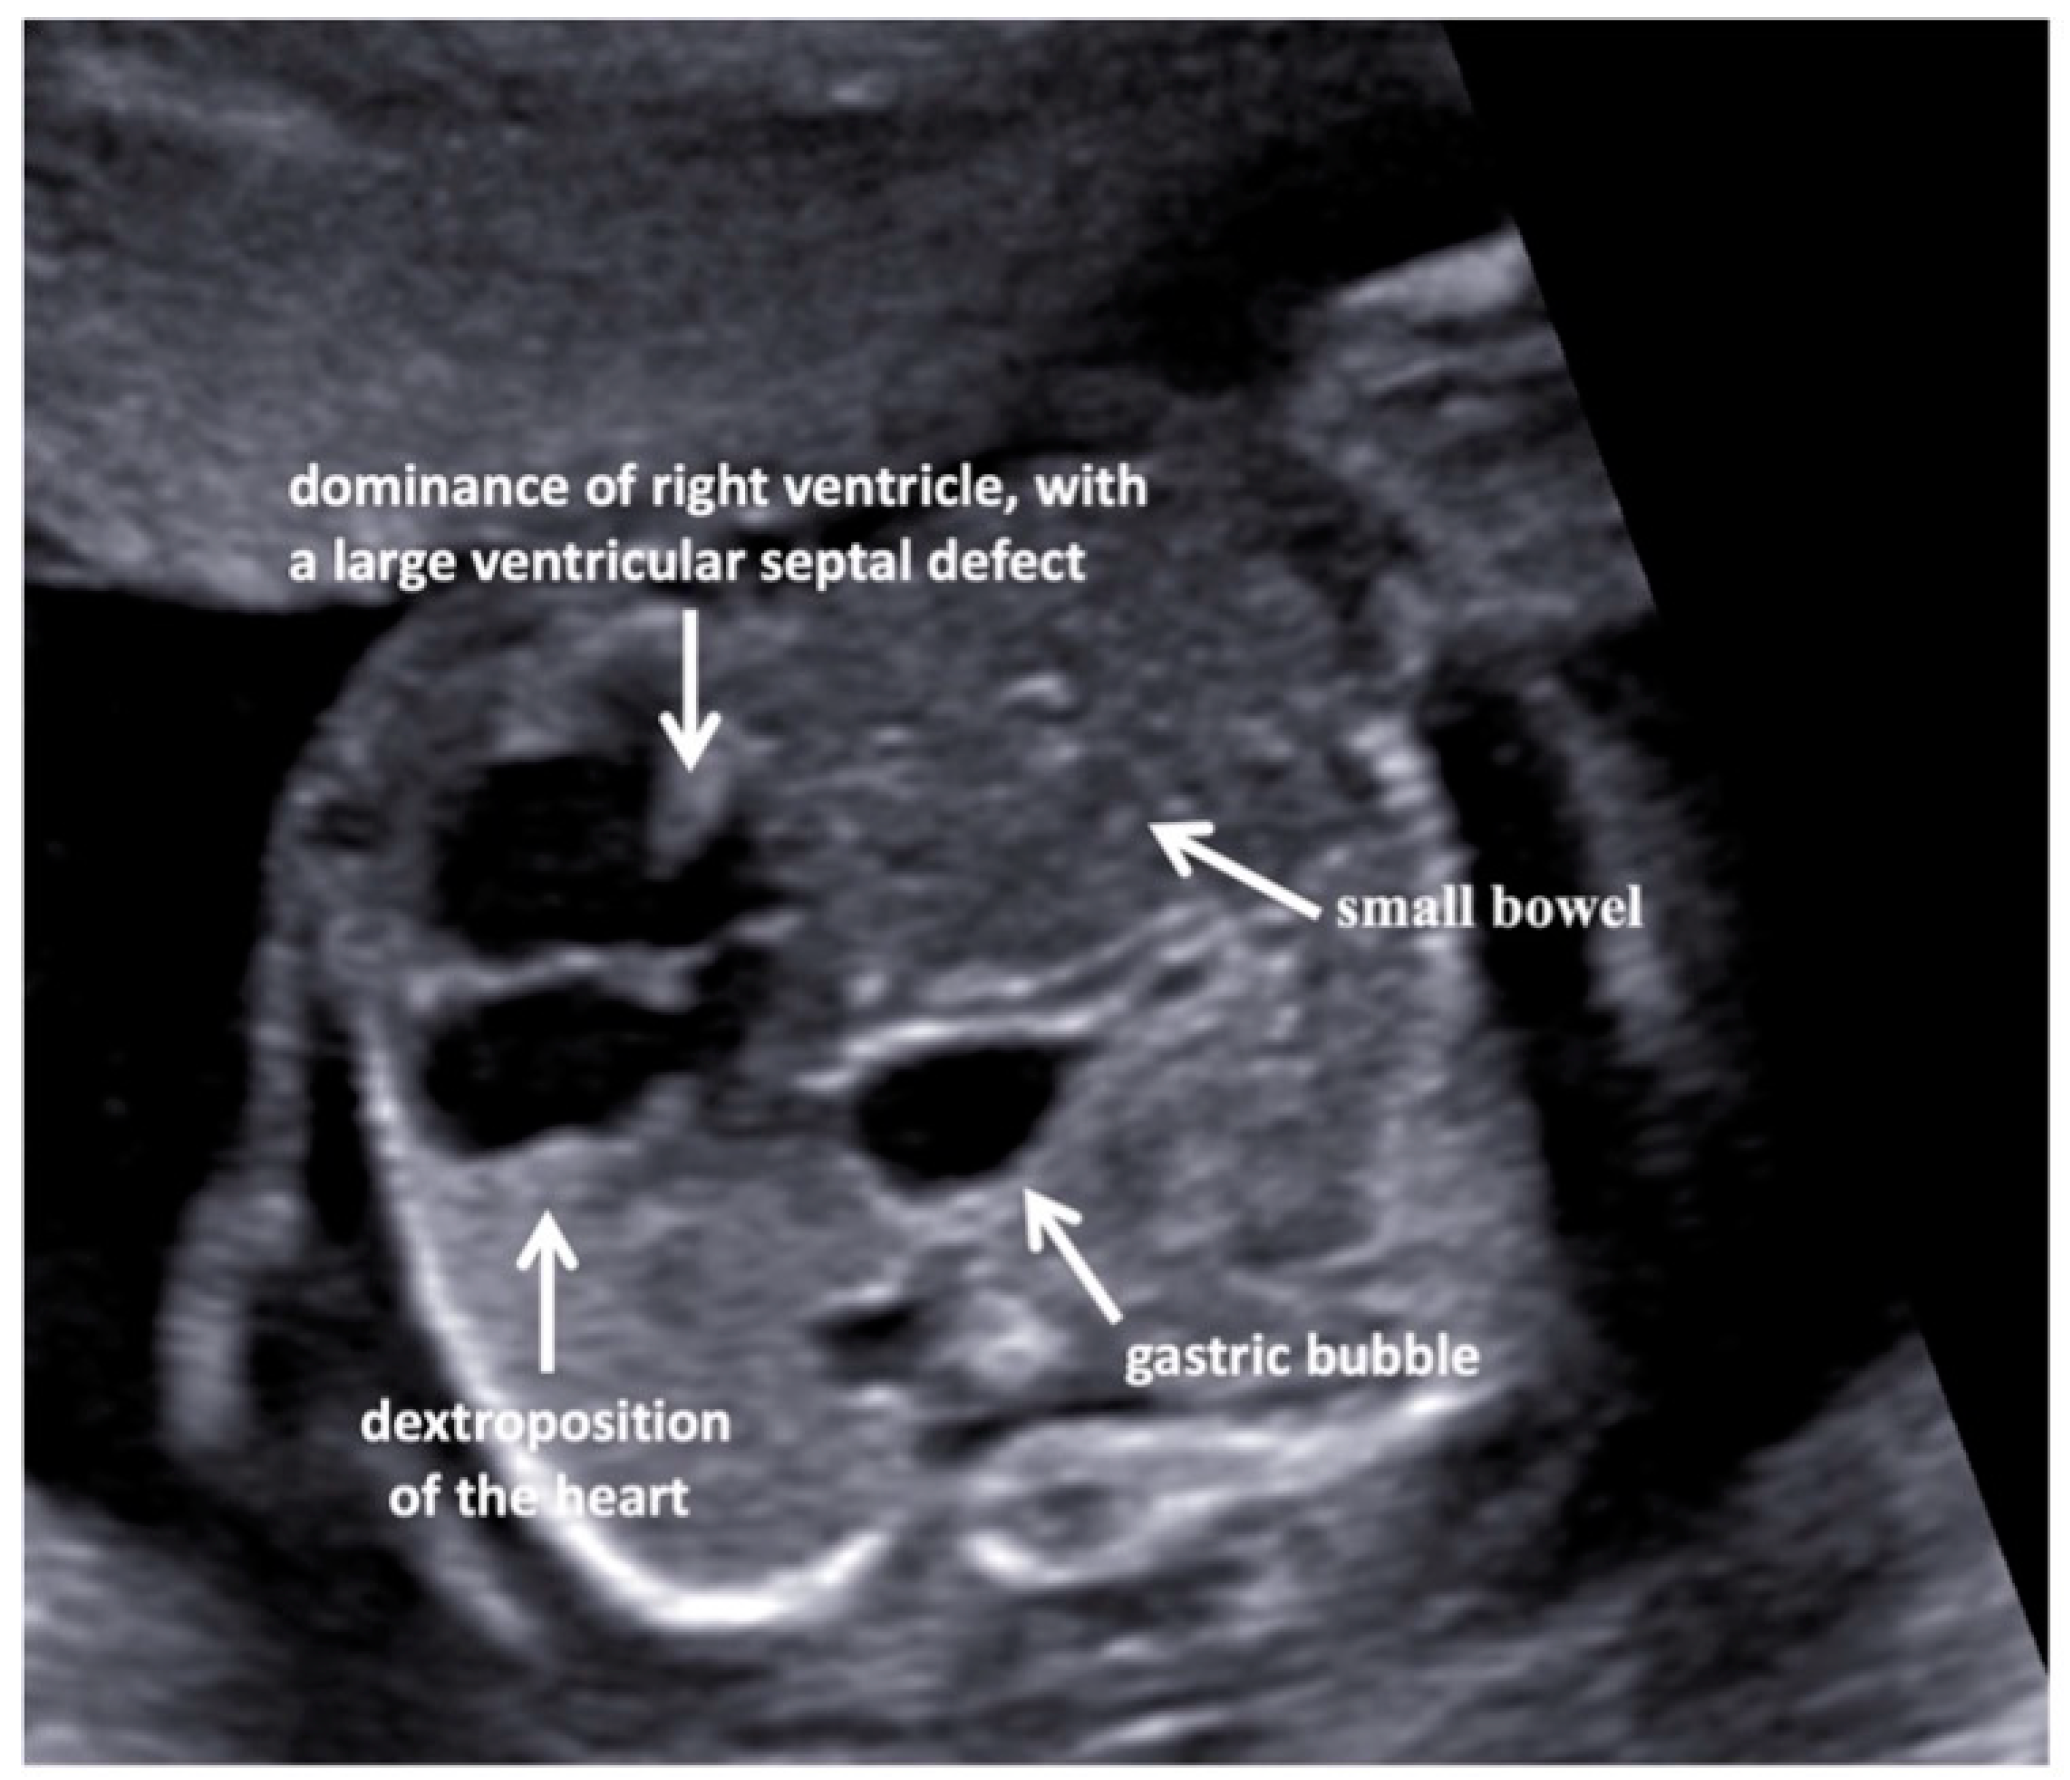

A fetal ultrasound (USA) in a 35-year-old Italian woman revealed multiple malformations despite first-trimester screening showing regular parameters (nuchal translucency, NT, 1.9 mm; crown-rump length, CRL, 7 mm). Additionally, the cell-free DNA screening test for fetal aneuploidy had a Z score in the normal range. The pregnancy was uneventful until the second level US examination at the 19th gestation week when the left-sided diaphragmatic hernia (CDH), dextroposition of the heart, and severe aortic coarctation associated with a ventricular septal defect, and a Dandy–Walker malformation (Figure 1 and Figure 2) were highlighted.

Figure 1. Axial view of the fetal thorax with dextroposition of the heart secondary to a diaphragmatic hernia on the left, at 20 weeks of pregnancy. The four-chamber view shows a dominance of the right ventricle, with a large ventricular septal defect. The gastric bubble is just behind the heart. The small bowel is visible within the left chest.